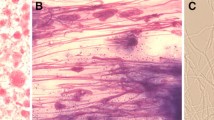

It is worth noting that, until now, the geopolitical isolation of several countries as well as the lack of microbiological facilities in many low-income areas of the world might have contributed to the difficulty in constructing an accurate map of worldwide histoplasmosis distribution. Table 2 shows studies from outside the USA [37–59], while Fig. 1 shows a world map constructed with estimated areas endemic to histoplasmosis based on case reports primarily among HIV-infected patients.

Geographic distribution of Histoplasma capsulatum var. capsulatum (purple) and H. capsulatum var. duboisii (shadow area). The circles indicate the number of published cases of autochthonous AIDS-associated histoplasmosis (via Scopus query). The majority of African cases have been observed outside Africa